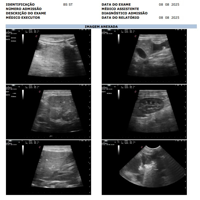

Na primeira semana de agosto, nosso cachorrinho Noah, um buldogue francês de 7 anos, começou a apresentar um certo inchaço na barriguinha. De primeira, achamos que poderia ser algum problema em algum órgão na região abdominal, como no fígado ou nos rins. Corremos para o veterinário para fazer uma ultrasssom, desconfiando de uma ascite abdominal (acúmulo de líquido), mas fomos surpreendidas ao descobrir que esse problema, na verdade, começou pelo coração.

Fizemos uma série de exames com cardiologistas e descobrimos a existência de um tumor no coração do Noah, tumor este que, até agora, ainda não conseguimos descobrir se é malígno ou benigno. Este tumor, quando inflamado, acaba gerando e acumulando líquido no pericárdio, ao redor do coração do Noah, e isso faz com que o coraçãozinho dele fique apertado, funcionando com dificuldade. O coração, por estar em sofrimento, acaba não conseguindo bombear sangue o suficiente para o restante do corpo, fazendo com que os órgãos fiquem sobrecarregados e que mais líquido se acumule, se espalhando também para a região abdominal. Mesmo já tendo feito cerca de quatro drenagens (sendo três no coração e uma no pulmão, que também já acumulou líquido), este problema fica indo e vindo, nos deixando desamparadas. Ele, quando está com líquido retido, não consegue deitar direito para dormir, fica dormindo sentado, perde o apetite, fica com a respiração pesada…